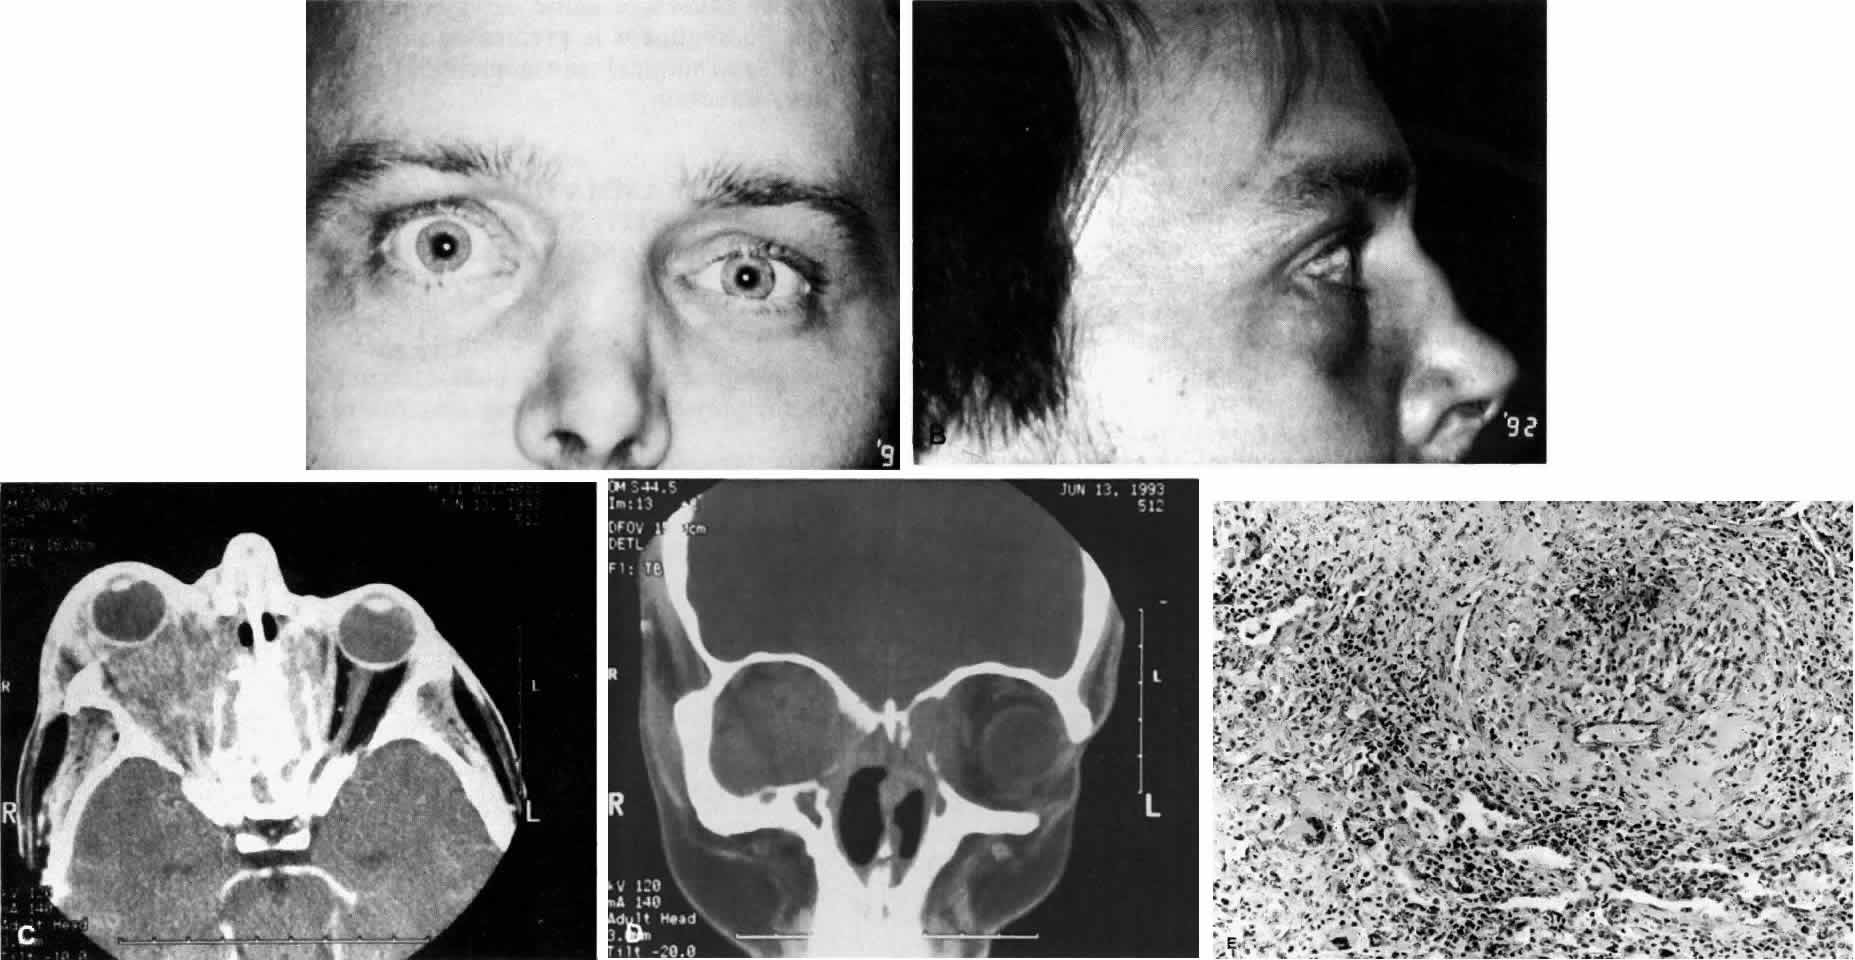

Fig. 10. A. This 68-year-old woman presented with acute orbital inflammation, pain, and diplopia. Clinical evaluation demonstrated a medial orbital mass. Biopsy of the orbital mass demonstrated significant vasculitic and granulomatous changes believed to be consistent with Wegener's granulomatosis. No systemic disease was present. B. Appearance of same patient after treatment with prednisone and cyclophosphamide demonstrating complete resolution of the inflammatory process.

Fig. 11. A. This 31-year-old man has had Wegener's granulomatosis for 2 years. His disease process is stable on chronic corticosteroid therapy. He has no evidence of systemic disease. Note right-sided proptosis and hyperglobus. B. Profile of same patient demonstrating collapse of nasal bridge from bony destruction secondary to Wegener's granulomatosis. Note presence of swelling in lower eyelid. C. Axial CT image from the same patient demonstrating significant bilateral disease and bony destruction. Despite the extent of the orbital process on the right, the patient does not have diplopia. D. Coronal CT image showing destruction of medial orbital walls, vomer, and orbital septum. E. Pulmonary biopsy specimen from patient with orbital signs contains an almost obliterated vessel to right of center and scattered giant cells on left (H&E, ×160).

Ocular manifestations include orbital inflammation, scleritis, keratitis, and uveitis. The ocular involvement can occur from extension of sinus and nasal lesions or from focal small vessel vasculitis.